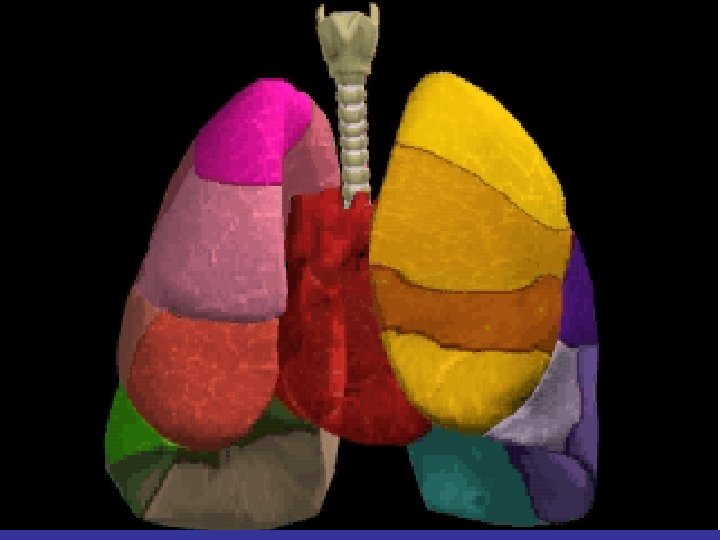

Lobes and Fissures